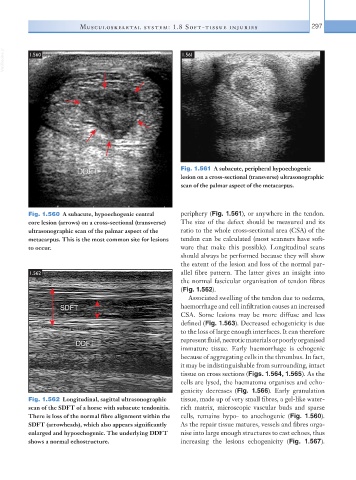

Fig. 1.561  A subacute, peripheral hypoechogenic

lesion on a cross-sectional (transverse) ultrasonographic

scan of the palmar aspect of the metacarpus.

Fig. 1.560  A subacute, hypoechogenic central   periphery (Fig. 1.561), or anywhere in the tendon.

core lesion (arrows) on a cross-sectional (transverse)   The size of the defect should be measured and its

ultrasonographic scan of the palmar aspect of the   ratio to the whole cross-sectional area (CSA) of the

metacarpus. This is the most common site for lesions   tendon can be calculated (most scanners have soft-

to occur.                                      ware that make this possible). Longitudinal scans

Fig. 1.562  Longitudinal, sagittal ultrasonographic   tissue, made up of very small fibres, a gel-like water-

scan of the SDFT of a horse with subacute tendonitis.   rich matrix, microscopic vascular buds and sparse

There is loss of the normal fibre alignment within the   cells, remains hypo- to anechogenic (Fig. 1.560).

SDFT (arrowheads), which also appears significantly   As the repair tissue matures, vessels and fibres orga-

enlarged and hypoechogenic. The underlying DDFT   nise into large enough structures to cast echoes, thus

shows a normal echostructure.                  increasing the  lesions echogenicity (Fig. 1.567).